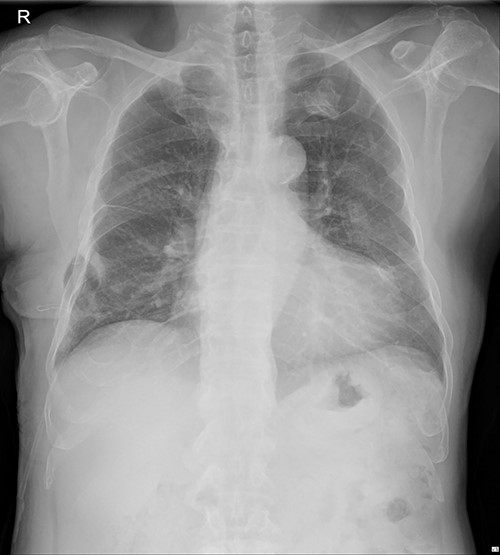

The patient visited the outpatient clinic on 07 March 2022, for stitches removal, complaining of mild discomfort on the operation site (Fig. 3.). Chest X-ray showed a large, localized submuscular emphysema between the rib cage and the SAM. The surgical wound was clear. Stitches were removed as planned, and the patient was asked to revisit the outpatient clinic 3 days later.

The submuscular emphysema, however, was increased in size, and the patient was eventually re-hospitalized. A small incision was made beneath the surgical wound under local anesthesia, and a 10 FR thoracic drainage catheter was carefully placed into the submuscular layer (Fig. 4.). Under 2 L of oxygen supplement, the submuscular emphysema gradually decreased over several days, and the patient was finally discharged on hospital Day 6 (Fig. 5). Since his last readmission, there have not been any more complications.